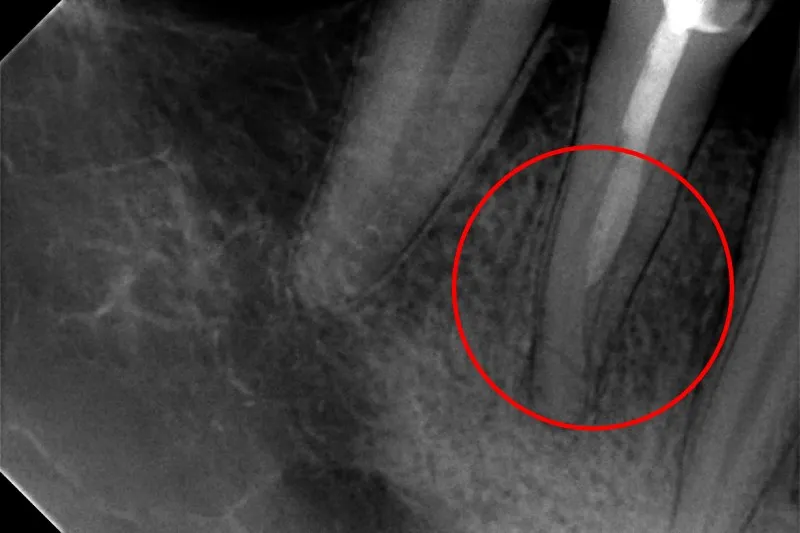

Innym poważnym problemem jest pęknięty korzeń zęba. Objawy mogą być podstępne i obejmować ból przy nagryzaniu, który często nasila się przy zwalnianiu nacisku, nadwrażliwość na zmiany temperatury, a czasem nawet obrzęk dziąsła w okolicy zęba. Na zdjęciu RTG pęknięcie może być widoczne jako cienka, ciemna linia. Niestety, nie zawsze jest łatwe do zdiagnozowania, a jego konsekwencje mogą być bardzo poważne, często prowadząc do utraty zęba.

Pęknięcia korzenia zęba to jedne z najtrudniejszych do leczenia problemów. Rozróżniamy pęknięcia pionowe i poziome. Niestety, pionowe pęknięcia mają zazwyczaj najgorsze rokowanie, ponieważ często biegną przez całą długość korzenia, dzieląc go na dwie lub więcej części. W takich przypadkach bakterie łatwo dostają się do głębszych tkanek, a ząb staje się niestabilny, co niestety bardzo często prowadzi do konieczności jego ekstrakcji.

Leczenie pękniętego korzenia zęba jest wyzwaniem i zależy od rodzaju, lokalizacji i rozległości pęknięcia. W niektórych, rzadkich przypadkach, jeśli pęknięcie jest niewielkie i nie obejmuje całej długości korzenia, można podjąć próbę leczenia kanałowego i wzmocnienia zęba. Częściej jednak, zwłaszcza przy pęknięciach pionowych, jedyną skuteczną metodą leczenia jest ekstrakcja zęba. Po usunięciu zęba, pacjent może rozważyć uzupełnienie braku za pomocą implantu lub mostu, aby przywrócić pełną funkcjonalność i estetykę uśmiechu.